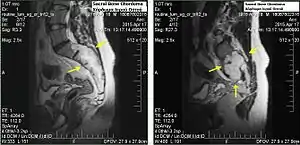

| MRI of extensive clival chordoma in 17-year-old male patient, axial view. Tumor in the nasopharynx extending from nasal cavity to brainstem posteriorly is clearly visible. | |